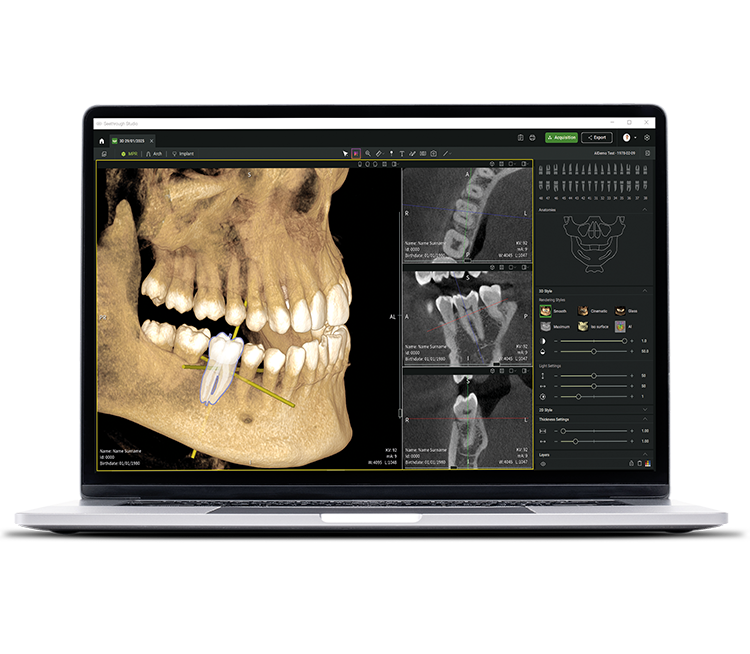

• Seethrough Studio

See tomorrow. See a new level.

Neben ausgereiften Hardware-Technologien ist die revolutionäre Seethrough Studio Software der entscheidende Faktor für den hohen Standard des gesamten W&H-Imaging Portfolios: Mit nützlichen Funktionen und fortschrittlichen Algorithmen ist Seethrough Studio eine Komplettlösung, die die Bildgebung und digitale Workflows in der Zahnmedizin auf ein neues Niveau hebt.

Integriertes Implantatplanungstool

Über die herausragende Bildqualitätund die intuitive Bedienung hinaus bietet Seethrough Studio zahlreiche nützliche Funktionen wie etwa das standardmäßig integrierte Implantatplanungstool für eine einfache Visualisierung und Vorbereitung der Behandlung.

KI-unterstützte Funktionen

Seethrough Studio nutzt verschiedene KI-Tools für eine noch bessere Bildgebung wie 3D-Volumenausrichtung, Zahnsegmentierung, Bogenliniengenerierung, automatische Nervenerkennung und hilfreiche Unterstützung bei der Pathologieerkennung.